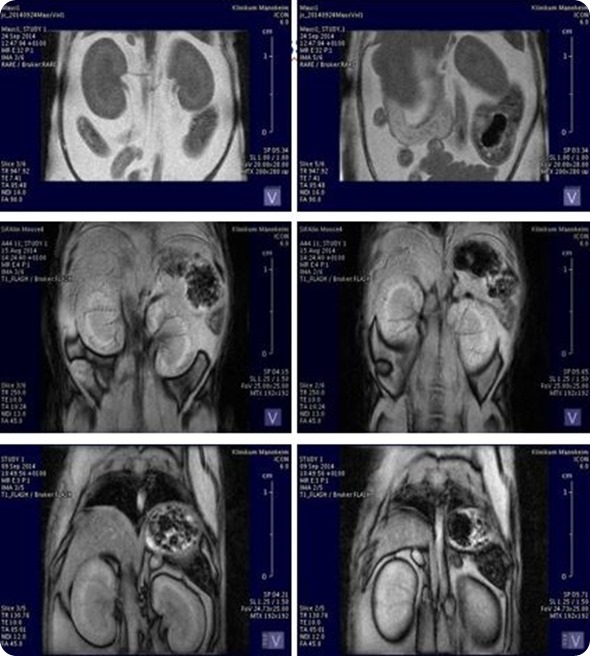

ICON: Organ volumetry and tissue characteristics

ICON: Organ volumetry and tissue characteristics. Image Credit: Bruker BioSpin Group

In the case of the MRI, it's mostly a combination with the PET system, which allows a better contrast in the brain or body and enables us to see the soft tissues better or to differentiate better between them in the body.